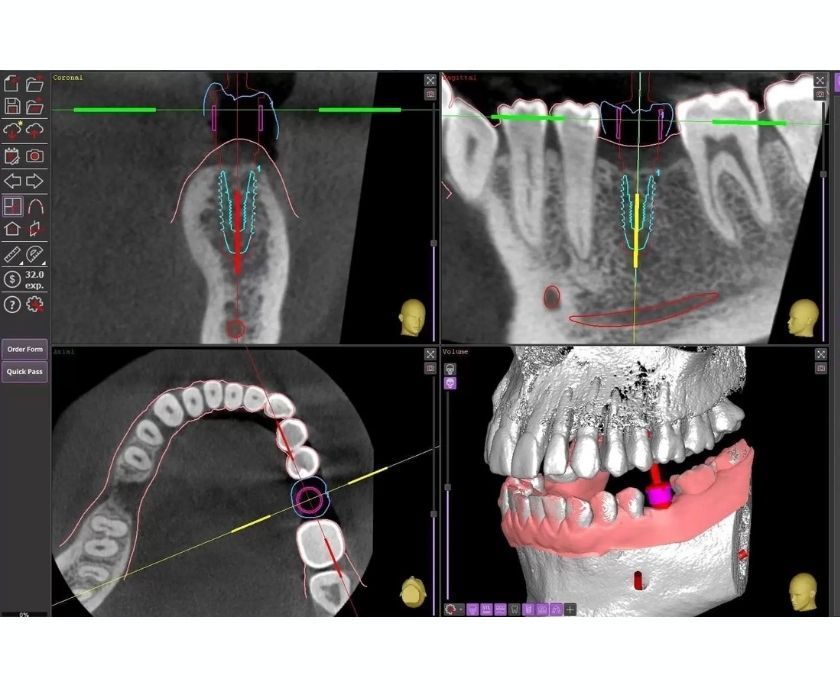

Sau khi chụp phim CT Conebeam 3D và quét dấu hàm kỹ thuật số, dữ liệu xương hàm và mô răng được tái tạo trong không gian ba chiều. Bác sĩ sẽ tiến hành lập kế hoạch đặt Implant trên phần mềm chuyên dụng, xác định vị trí tối ưu cả về mặt sinh học lẫn phục hình.

Máng hướng dẫn phẫu thuật được thiết kế dựa trên kế hoạch này và in bằng công nghệ 3D. Trong quá trình phẫu thuật, máng sẽ được đặt cố định trên cung răng, giúp định hướng mũi khoan và trụ Implant theo đúng vị trí đã tính toán trước. Nhờ đó, bác sĩ không cần mở lợi để “nhìn trực tiếp” mà vẫn kiểm soát chính xác toàn bộ quá trình.

CT CONEBEAM 3D – NỀN TẢNG CỦA IMPLANT AN TOÀN VÀ ÍT ĐAU

CT Conebeam là công nghệ chẩn đoán hình ảnh ba chiều chuyên biệt cho vùng hàm mặt. Khác với phim X-quang hai chiều truyền thống, Conebeam cho phép đánh giá đồng thời chiều cao, chiều rộng và chiều sâu của xương hàm, cũng như xác định chính xác vị trí các cấu trúc giải phẫu quan trọng như dây thần kinh, xoang hàm và mạch máu.

Nhờ dữ liệu 3D, bác sĩ có thể lựa chọn loại Implant phù hợp, tránh các vùng nguy cơ và tối ưu hóa hướng đặt Implant ngay từ đầu. Điều này không chỉ giúp tăng tỷ lệ tích hợp xương mà còn hạn chế tối đa các biến chứng sau phẫu thuật.